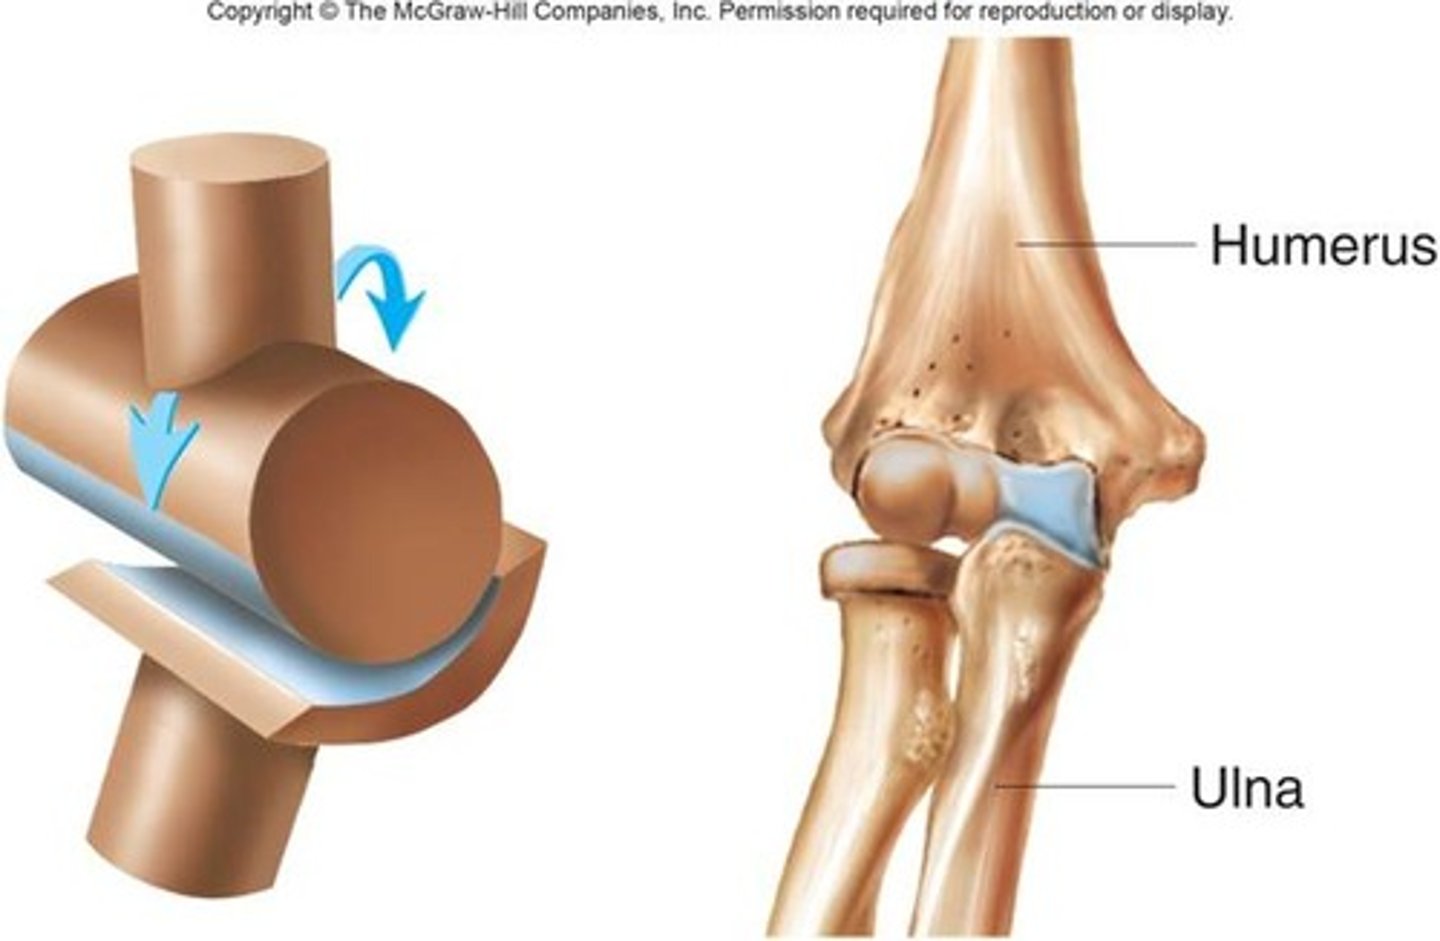

Hinge synovial joint

allow movement around one axis that passes transversely through the joint

-permits extension and flexion

ex: elbow joint